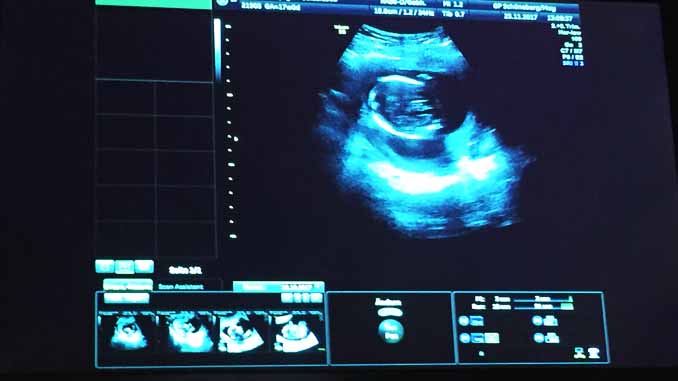

Những người sắp làm bố mẹ đều mong chờ giây phút nhìn thấy mặt và cử động của con yêu khi còn trong bụng mẹ. Do đó, ngoài 3 thời điểm siêu âm được bảo hiểm chi trả theo luật, nhiều người sẵn sàng bỏ tiền để được thấy con yêu nhiều hơn. Đây cũng là một dịch vụ giúp nhiều phòng khám thu về khoản tiền không nhỏ.

Tuy nhiên, từ năm 2021, Đức cấm tất cả hình thức siêu âm không cần thiết cho chuẩn đoán y khoa. Có nghĩa, ngoài 3 lần siêu âm cơ bản theo luật định, bố mẹ không được yêu cầu siêu âm 3D hay 4D chỉ vì muốn được nhìn thấy con. Dịch vụ siêu âm tư nhân sẽ bị cấm từ năm 2021. Ngay cả việc đo cơn gò thai kì không cần thiết cũng bị cấm.

Quy định cấm này được quy định trong điều 10, Luật bảo vệ tia bức xạ mới được cập nhật ngày 31-12-2018. Tuy nhiên, trong luật không nói rõ liệu việc siêu âm có gây hại cho thai nhi không. Hiện nay, vẫn chưa có nghiên cứu có ý nghĩa lâm sàng về việc sóng âm gây ảnh hưởng xấu hay dị tật đến thai.

Theo Hiệp hội bảo vệ tia bức xạ Strahlenschutzkommission, không thể loại bỏ 100% khả năng này. Trên thực tế, để có những tấm hình siêu âm 3D và 4D rõ nét, cần phải trang bị máy móc năng suất cao, đồng nghĩa sóng âm mạnh hơn. Luật có hiệu lực từ năm 2021.